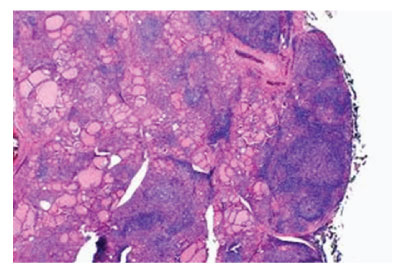

Figure 1: Hashimoto’s thyroiditis demonstrating a polyclonal inflammatory exudate of lymphocytes and plasma cells with configuration of germinal centres traversed with fibrous tissue and few intervening thyroid follicles [5].

Lymphocytic infiltration of thyroid parenchyma is graded from zero to three+, contingent to intensity of chronic inflammatory cell infiltrate as mature lymphocytes. However, previously mentioned grading appears non–concurrent to diverse clinical manifestations or prognostic outcomes. Upon gross examination, diffuse, symmetric enlargement of thyroid gland is observed. Occasionally, thyroid gland is nodular and asymmetrically enlarged [2,3]. Glandular atrophy may occur. The gland is encapsulated and gross weight varies from 25 grams to 250 grams. Pyramidal lobe may be prominent. Thyroid gland may adhere to although can be detached from surrounding structures and soft tissue. Cut surface is tan to yellow with enhanced interlobular fibrotic tissue and simulates lymph node. Focal necrosis or calcification is absent [2,3]. Upon microscopy, an extensive infiltrate of mature lymphocytes with configuration of germinal centres is observed. Invading lymphocytes are predominantly comprised of T lymphocytes and appear admixed with polyclonal plasma cells. Occasionally, lesion may be nodular [2,3]. Thyroid epithelial cells appear imbued with enlarged or overlapping nuclei. Few nuclei may demonstrate partial nuclear clearing. Additionally, enlarged squamous cell nests, hyperplastic lymphoid follicles and foci of ductal metaplasia may be discerned. Giant cell reaction may ensue [2,3].

Atrophic thyroid follicles abundantly coated with Hürthle cells or oncocytes are observed. Colloid is appropriately maintained. Fibrosis is enhanced, intra–parenchymal and confined by thyroid capsule. Foci of squamous metaplasia emerging within follicular epithelium may require distinction from solid epithelial cell nests [2,3]. Tumefaction may exhibit preliminary, focal, oxyphilic metaplasia of follicular epithelial cells. Nodular tumour configuration may ensue. Thyroid parenchyma is gradually replaced with aforesaid cellular content [2,3]. Cells of Hashimoto’s thyroiditis appear immune reactive to high molecular weight keratin or p63. Elevated kappa/lambda ratio occurs due to enhanced production of kappa light chains secreted by plasma cells [4,5] .